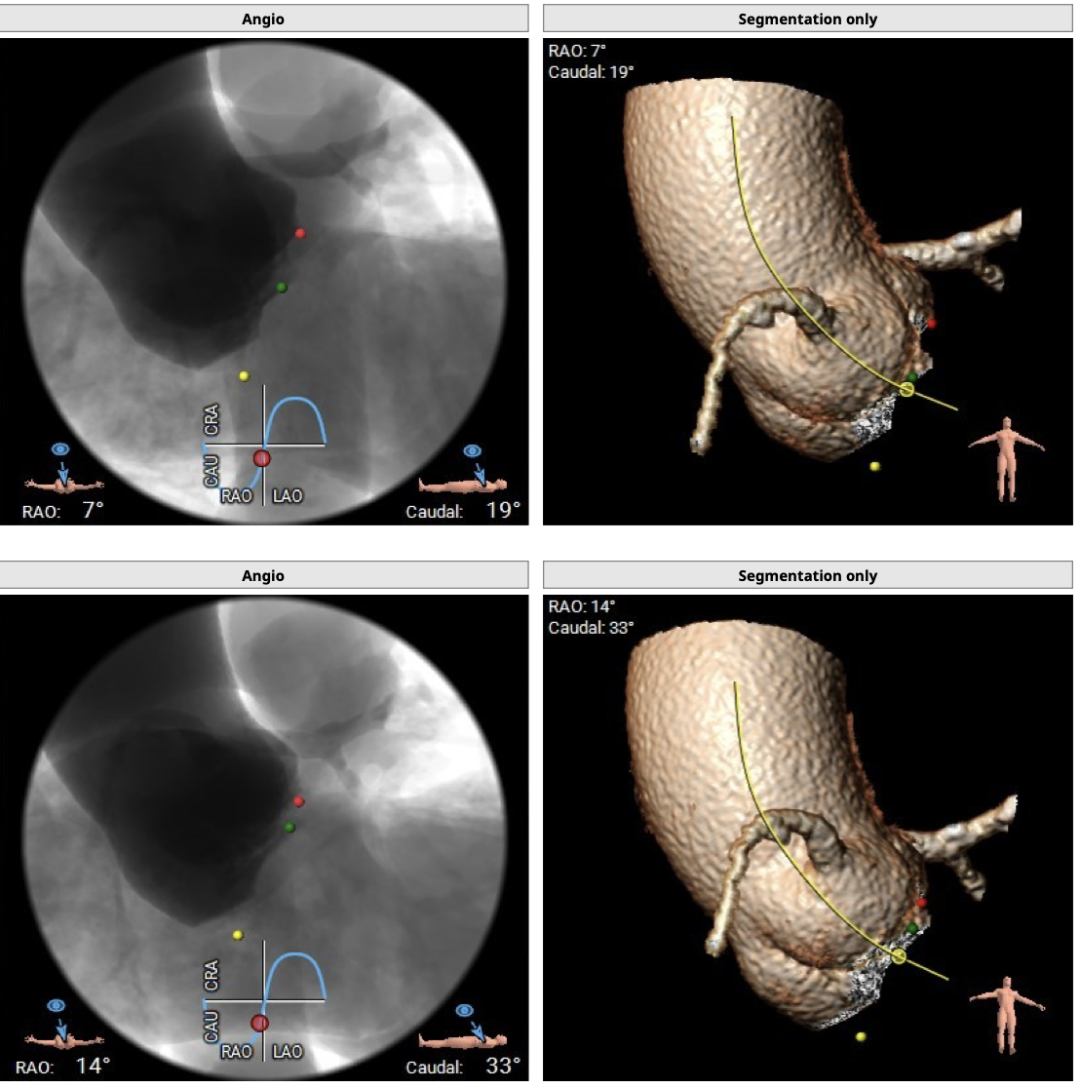

术中建议造影角度RAO:7°,CAU:19°(其它参考角度如下图):